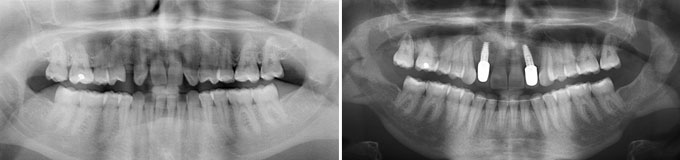

Implants multiples pour éviter les bridges et redonner des dents individuelles au patient avec traitement d’une maladie parodontale.

Implants multiples pour éviter les bridges et redonner des dents individuelles au patient. État final.